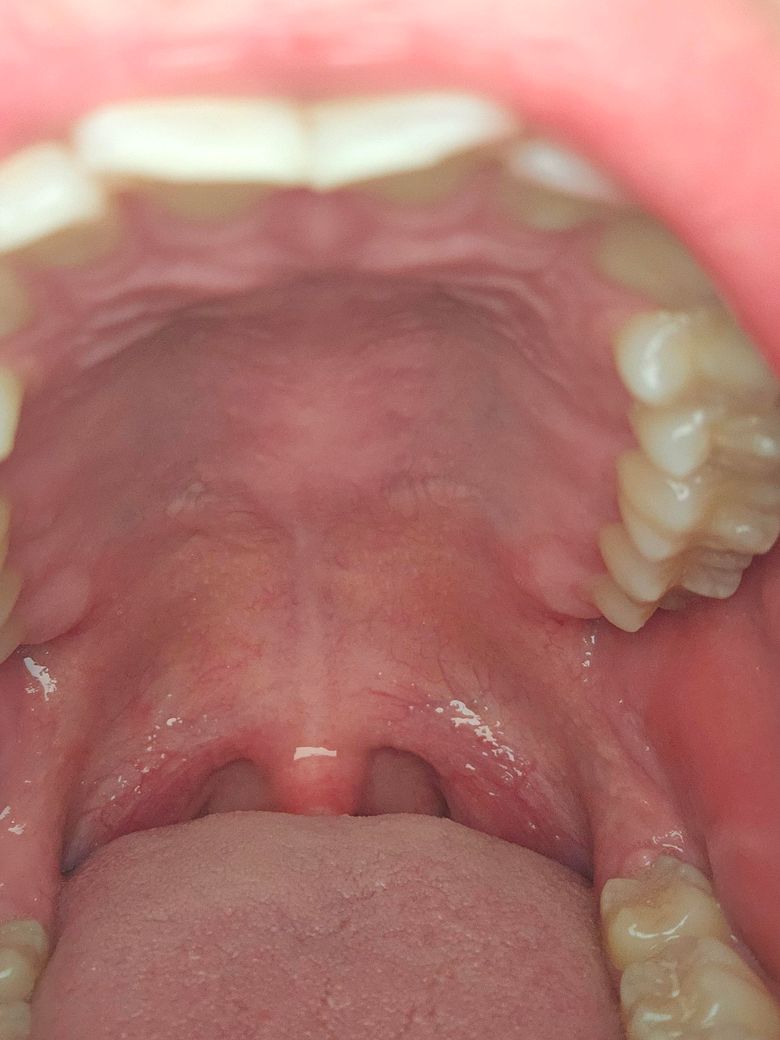

혹시 이게 하악 골융기 인가요 골융기가 맞다면 어떻게 해야 하나요?

오늘 갑자기 자다가 오른쪽 아래를 혀로 만졌는데 볼록 하길래 봤더니 오른쪽만 이렇게 튀어 나와있습니다... 아프지는 않고 딱딱한데 알아보니까 골융기 그런거 같더라구요.. 혹시 골융기가 맞을까요? 맞다면 어떻게 해야 할까요?

사진으로 봤을때는 별로 안커보이는데 거울로 보니까 좀 큰거 같아요..